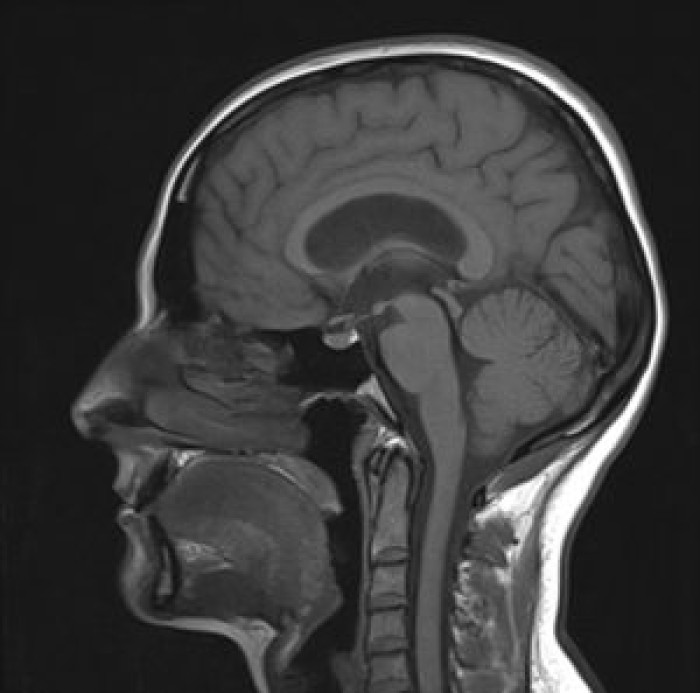

Bah tout autant que le ciel est bleu et l'herbe verte, là c'est une radiographie sans l'ombre d'un doute. Un IRM ce visualise par des vue en "coupe" Un IRM ça ressemble à ça :